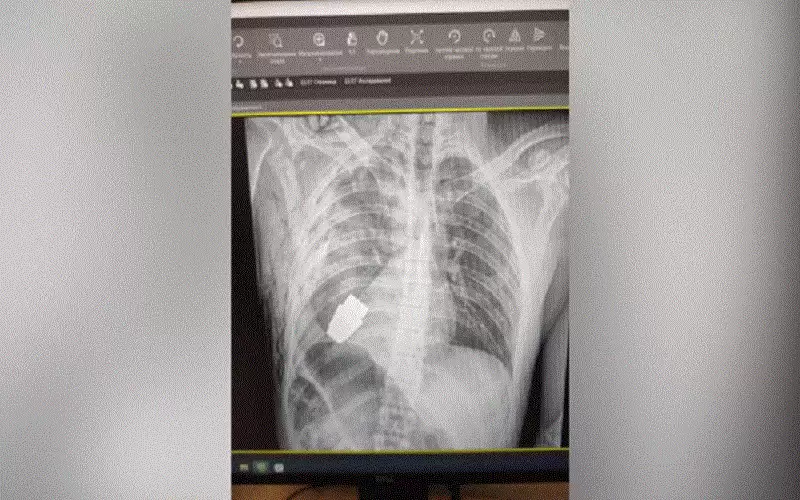

إنقاذ طفل سعودي من الموت في اسطنبول